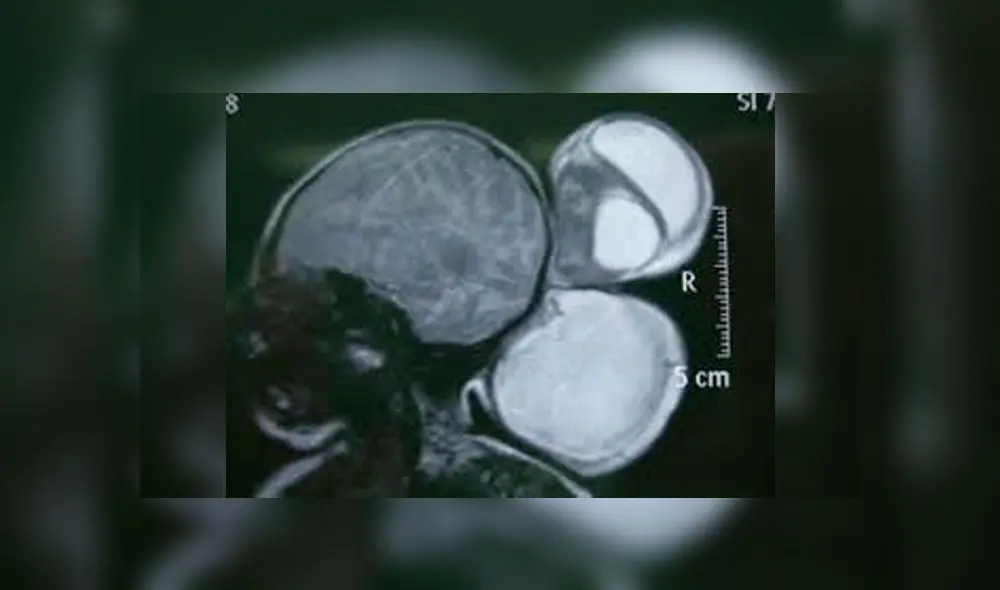

Los médicos de India han quedado sorprendidos ante el nacimiento de una niña con los dos grandes bultos salientes de la parte posterior de su cabeza, algo que, en conjunto, se ve como tres cabezas en un pequeño cuerpo . Al parecer, se trata de un caso notable de encefalocele, una anomalía que suele presentar solo un bulto. A pesar de eso, la niña puede sobrevivir.

“El cuerpo del niño no se ha desarrollado completamente. Realizaremos una resonancia magnética y luego realizaremos una cirugía para separar las cabezas”, afirmó Rajesh Thakur, jefe del Superintendente Médico del Hospital de Etah.

Las condiciones médicas de la recién nacida corresponden a la anomalía denominada encefalocele, la cual se ha reportado en diversos casos en todo el mundo.

Según Centros para el Control y Prevención de Enfermedades (CDC), el encefalocele es un tipo de defecto de nacimiento raro del tubo neural que afecta el encéfalo. Esta parte del cráneo no se ha formado correctamente (debió cerrarse entre la tercera y cuarta semana de gestación), por lo que una parte del tejido cerebral y las estructuras asociadas salen fuera de la cabeza, formando una o más protuberancias.

Según las estadísticas, los neonatos diagnosticados con este defecto congénito tienen una tasa de supervivencia del 55%, por lo que la niña con 'tres cabezas’ nacida en India podría sobrevivir, siempre y cuando se realice una cuidadosa operación que extraiga los bultos.